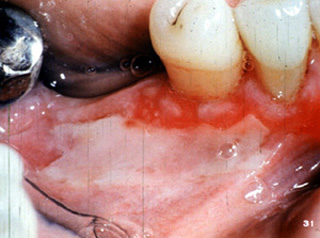

Aquí hay simplemente una vesícula intacta en la encía lingual superior